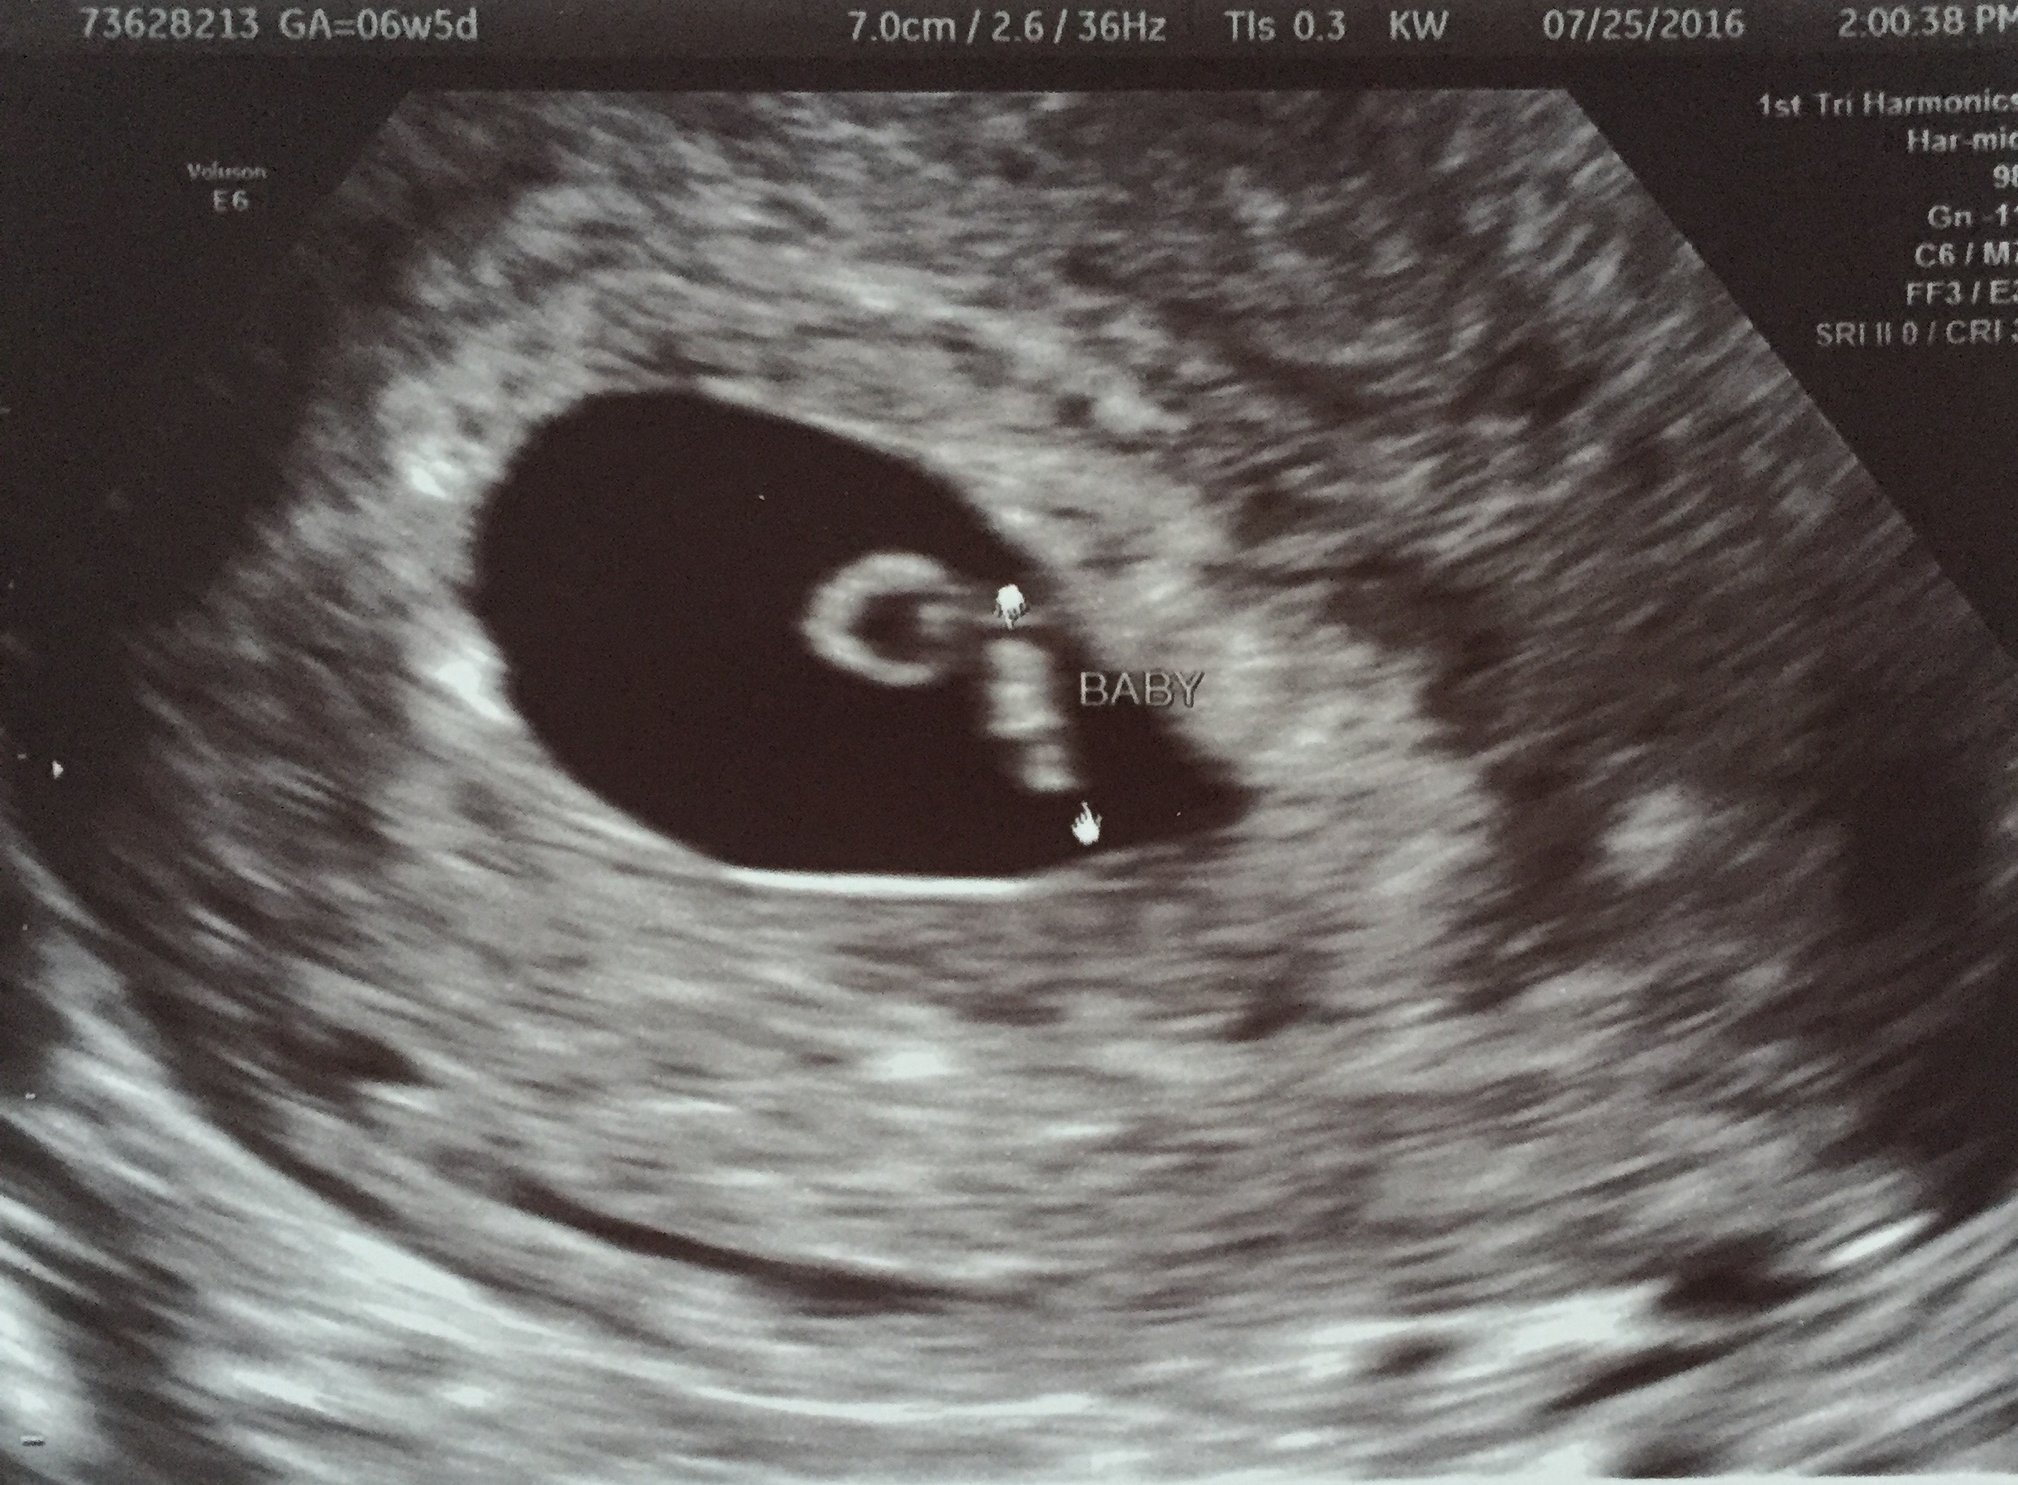

Had my first ultrasound today! Based on LMP I'm at 6w5d and by O at 6w2d and baby is measuring right at 6w2d! Doctor said he is going to keep my DD based on LMP though. Gotta admit, was kinda sad I only saw one baby in there after seeing all the twinsies on here this last week, but I'm glad I have a healthy little baby growing! I go back next week for another ultrasound and consult with MFM